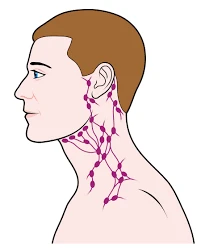

Компанія Transgene завершила рандомізацію TG4050 у фазі 2 клінічного випробування. Це терапевтична вакцина на основі неоантигенів. Вона призначена для ад’ювантного лікування раку голови та шиї. Вивчення оцінює її ефективність після операції та хіміорадіотерапії.

Рак голови та шиї часто рецидивує. Стандартне лікування включає операцію. Додають хімію та радіацію. Ад’ювантна терапія запобігає поверненню хвороби.

Рак голови та шиї – серйозна проблема. HPV-негативні форми агресивні. Рецидиви трапляються у 30-50% випадків. Нові методи потрібні терміново.